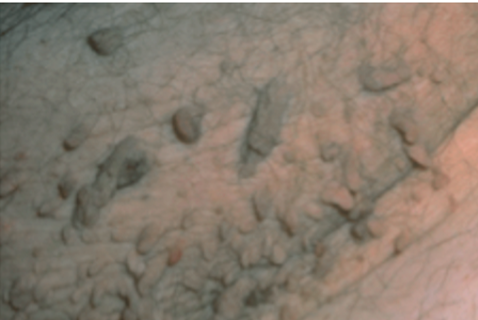

毛角化病(KP)是一种良性皮肤病,其特征为粉红色、红色、单形、毛囊性丘疹,常见于伸臂、大腿、臀部和面颊 。毛周角化病在通俗 人群中极为常见,但在特应性皮炎和T2DM患者中发生频率更高,涉及规模更广。在KP中视察到的角化太过和炎症转变 的机制尚不清晰 ,可能是多因素的,高雄激素血症作为高胰岛素血症的效果 ,可能在KP中起主要 作用,由于 循环雄激素升高是已知的毛囊皮脂腺单元角质形成细胞增殖的驱动因素。对这一理论的支持包罗青春期雄激素水平到达峰值时经常泛起的KP的临床增大。此外,一项研究发现,青少年1型糖尿病患者的KP发病率高于康健年岁 匹配的对照组。KP最有用 的治疗要领似乎是激光治疗,尤其是Q开关Nd:YAG激光。许多局部治疗要领被用于治疗KP,但效果有限,包罗矿物油、他克莫司、壬二酸和水杨酸等